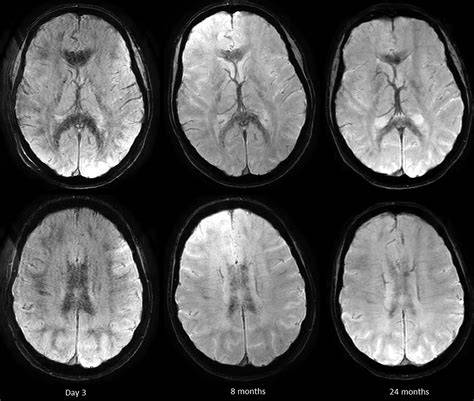

3. High Altitude Cerebral Edema (HACE): Pembengkakan Otak

HACE adalah bentuk paling parah dan mengancam nyawa. Kondisi ini terjadi ketika cairan menumpuk di dalam otak, menyebabkan pembengkakan . Gejalanya bisa berkembang cepat dari ringan menjadi kritis dalam hitungan jam.

Gejala HACE meliputi:

- Sakit kepala hebat yang tidak mereda

- Kebingungan dan disorientasi

- Gangguan koordinasi jalan (ataksia) atau berjalan sempoyongan seperti mabuk

- Penurunan kesadaran hingga koma